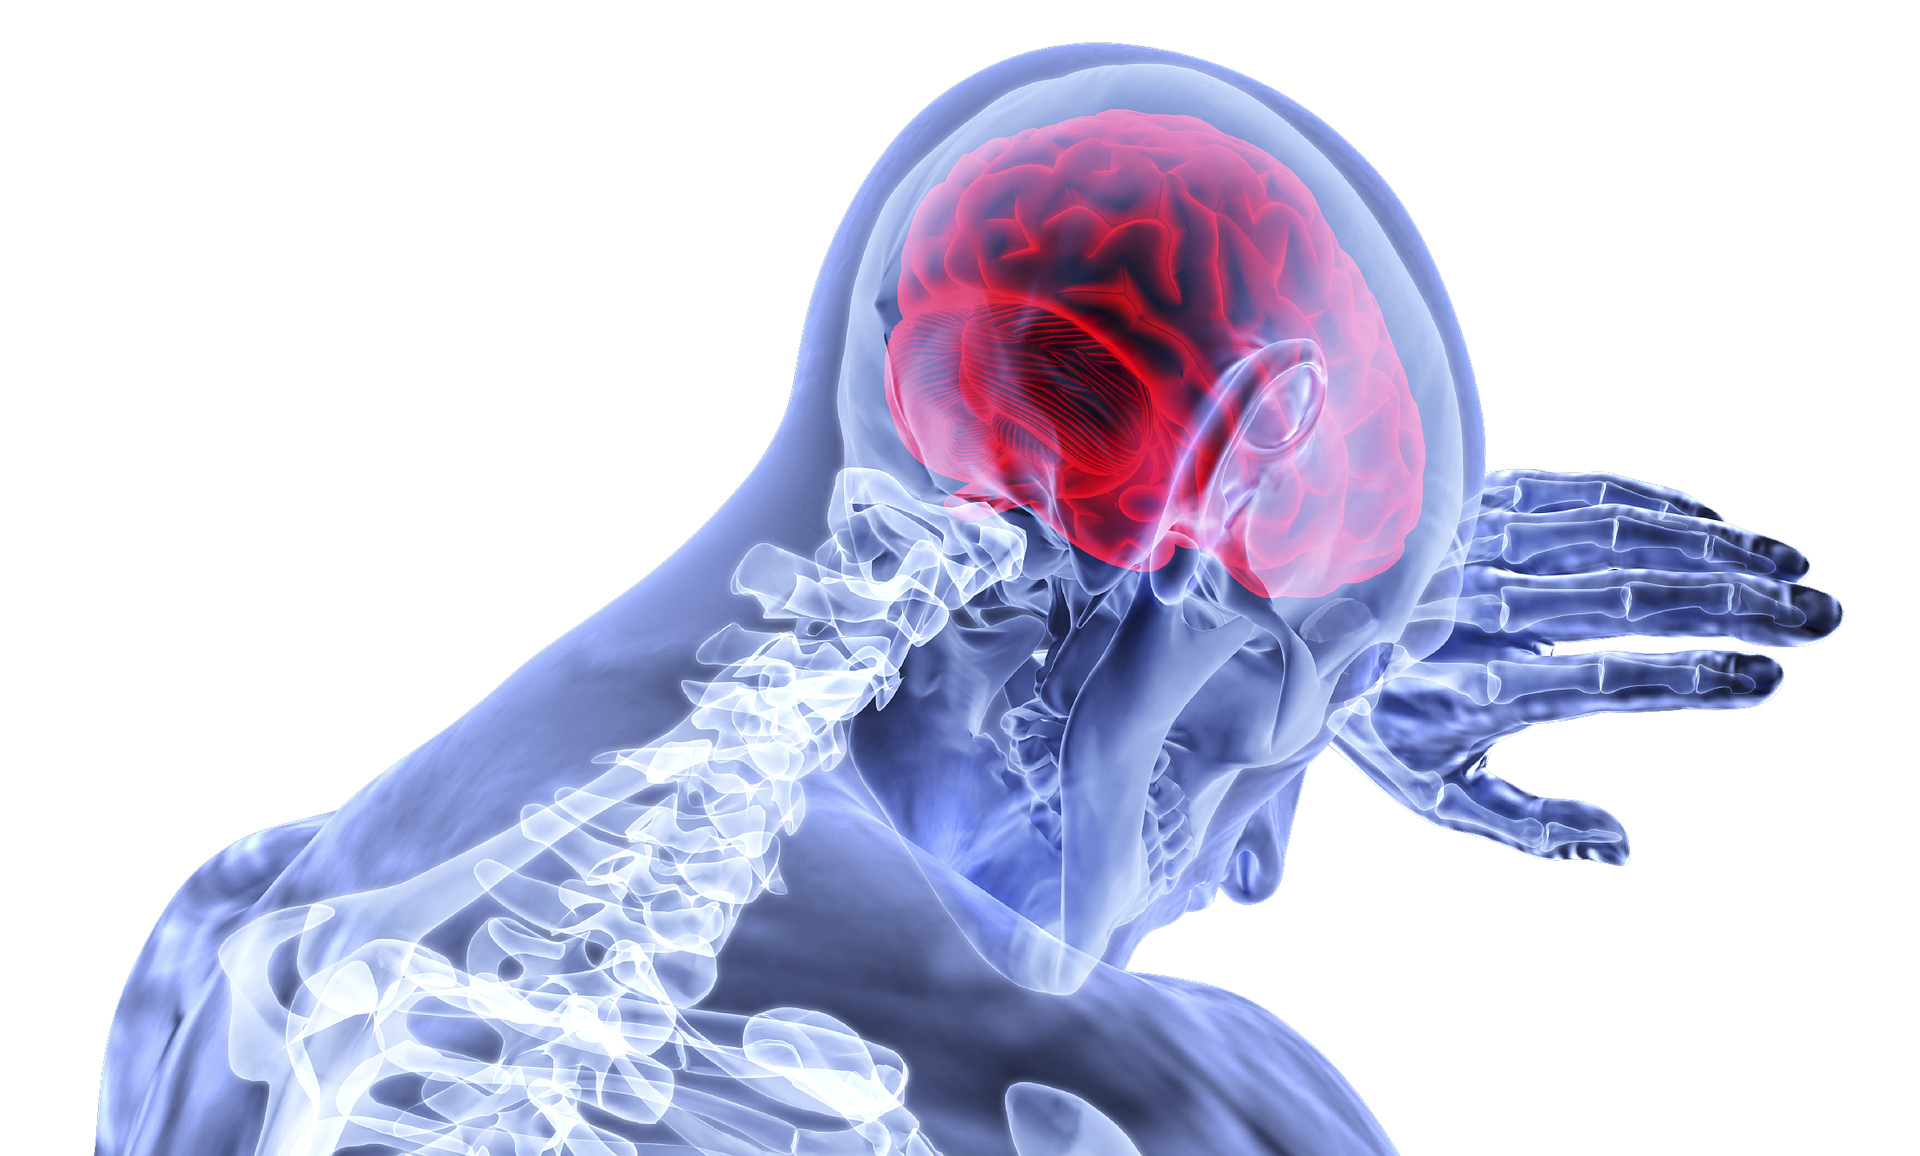

Хвороба судин головного мозку є одним з найбільш поширених неврологічних розладів в літньому віці. Інсульт виникає через зміни кровотоку мозку, що почався через розвиток судинної слабкості. Захворювання складно діагностувати без апарату МРТ, пише Neurobiology of Aging.

"Наша робота показує, що часто людей з вищим ризиком інсульту не могли зосередитися на конкретному завданні, поставленої ним в рамках нейропсихологического тесту. Якщо людина помічає розсіяний стан – це привід для термінового звернення до лікаря", – розповів автор дослідження Аян Дей.

Людям, які відчувають розсіяність терміново потрібно до лікаря//pixabay.com

Вчені довели свою теорію, провівши дослідження за участы 54 добровольців від 55 до 80 років з одним із чинників, який збільшував вірогідність розвитку інсульту: апное, куріння, високий рівень холестерину і тиск. Захворювання судин діагностувалося за допомогою сканування судин мозку і білої речовини на апараті МРТ.